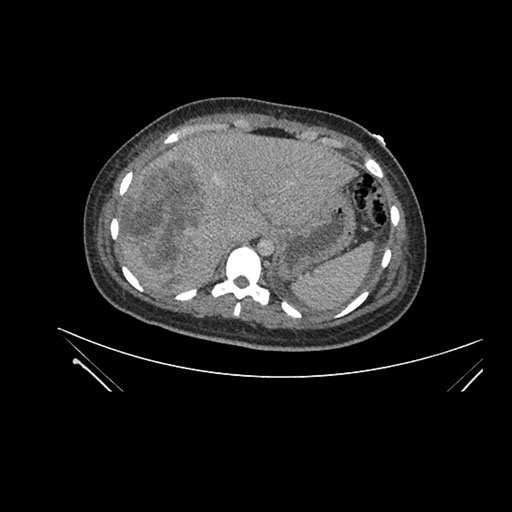

Axial Arterial